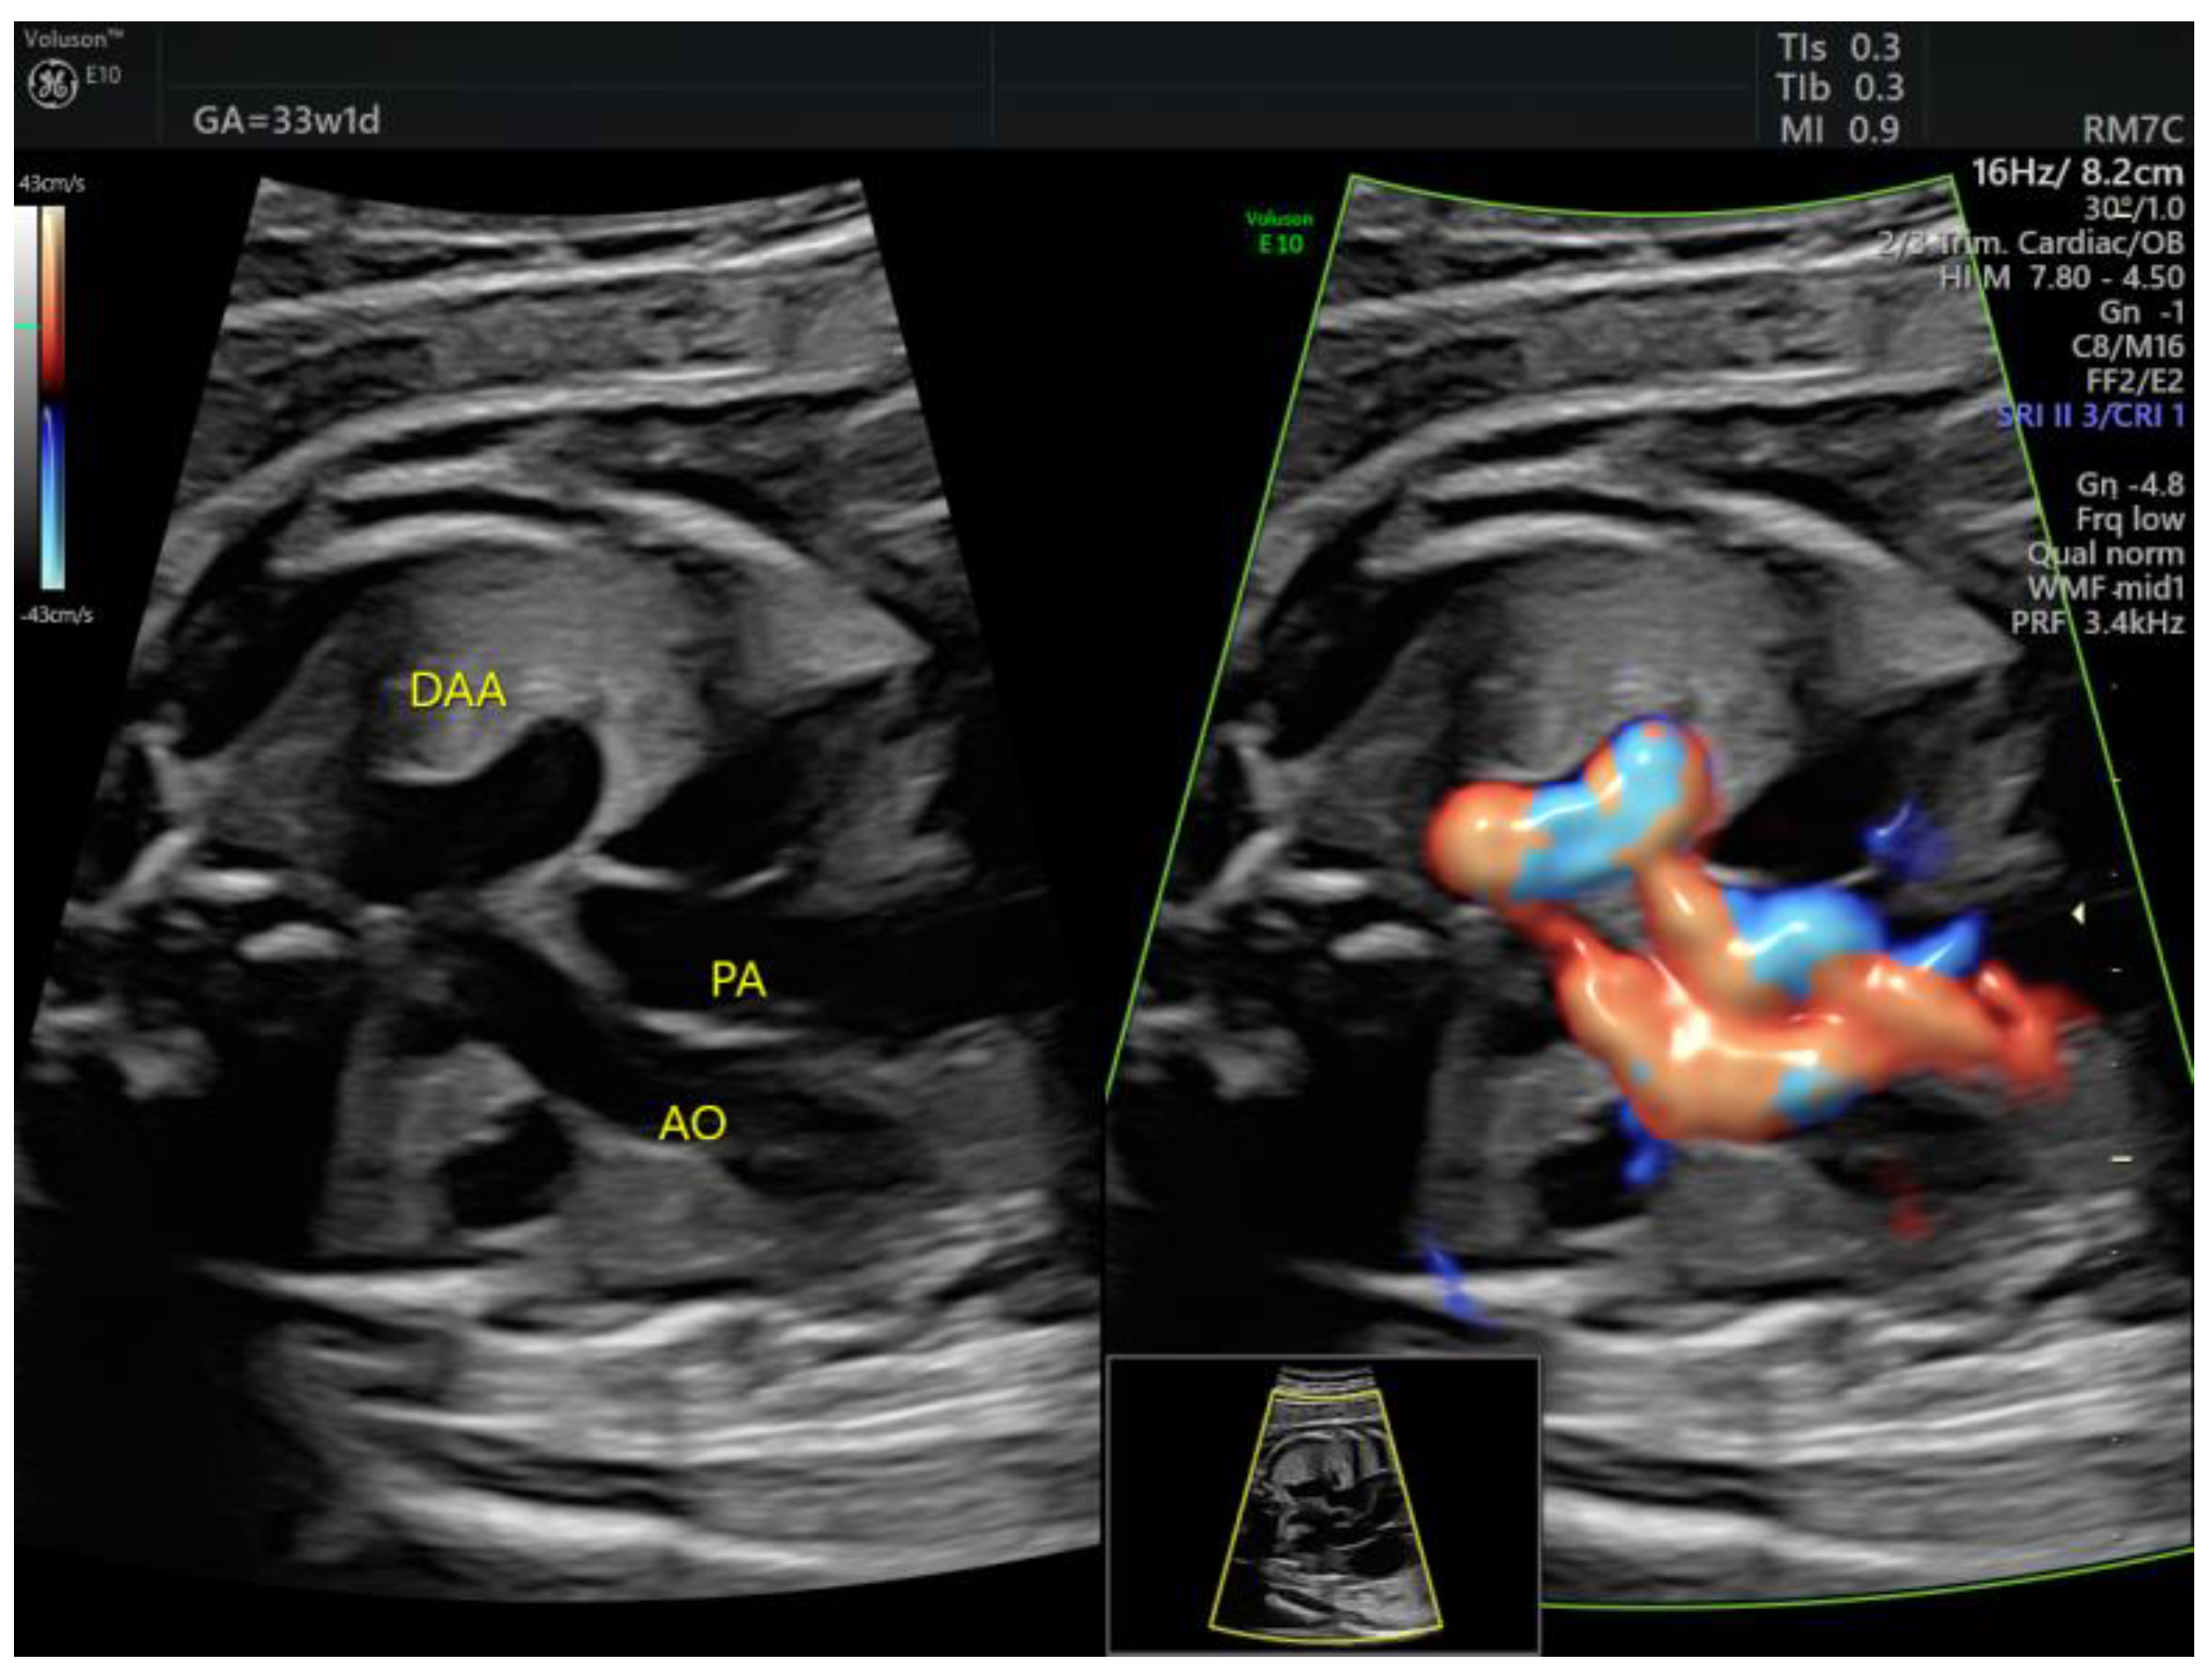

| DAA | 1 | Tortuous DA at 20 w + late FGR | - | 3VT | + | 0 | 0 | 1 | 1/1 |